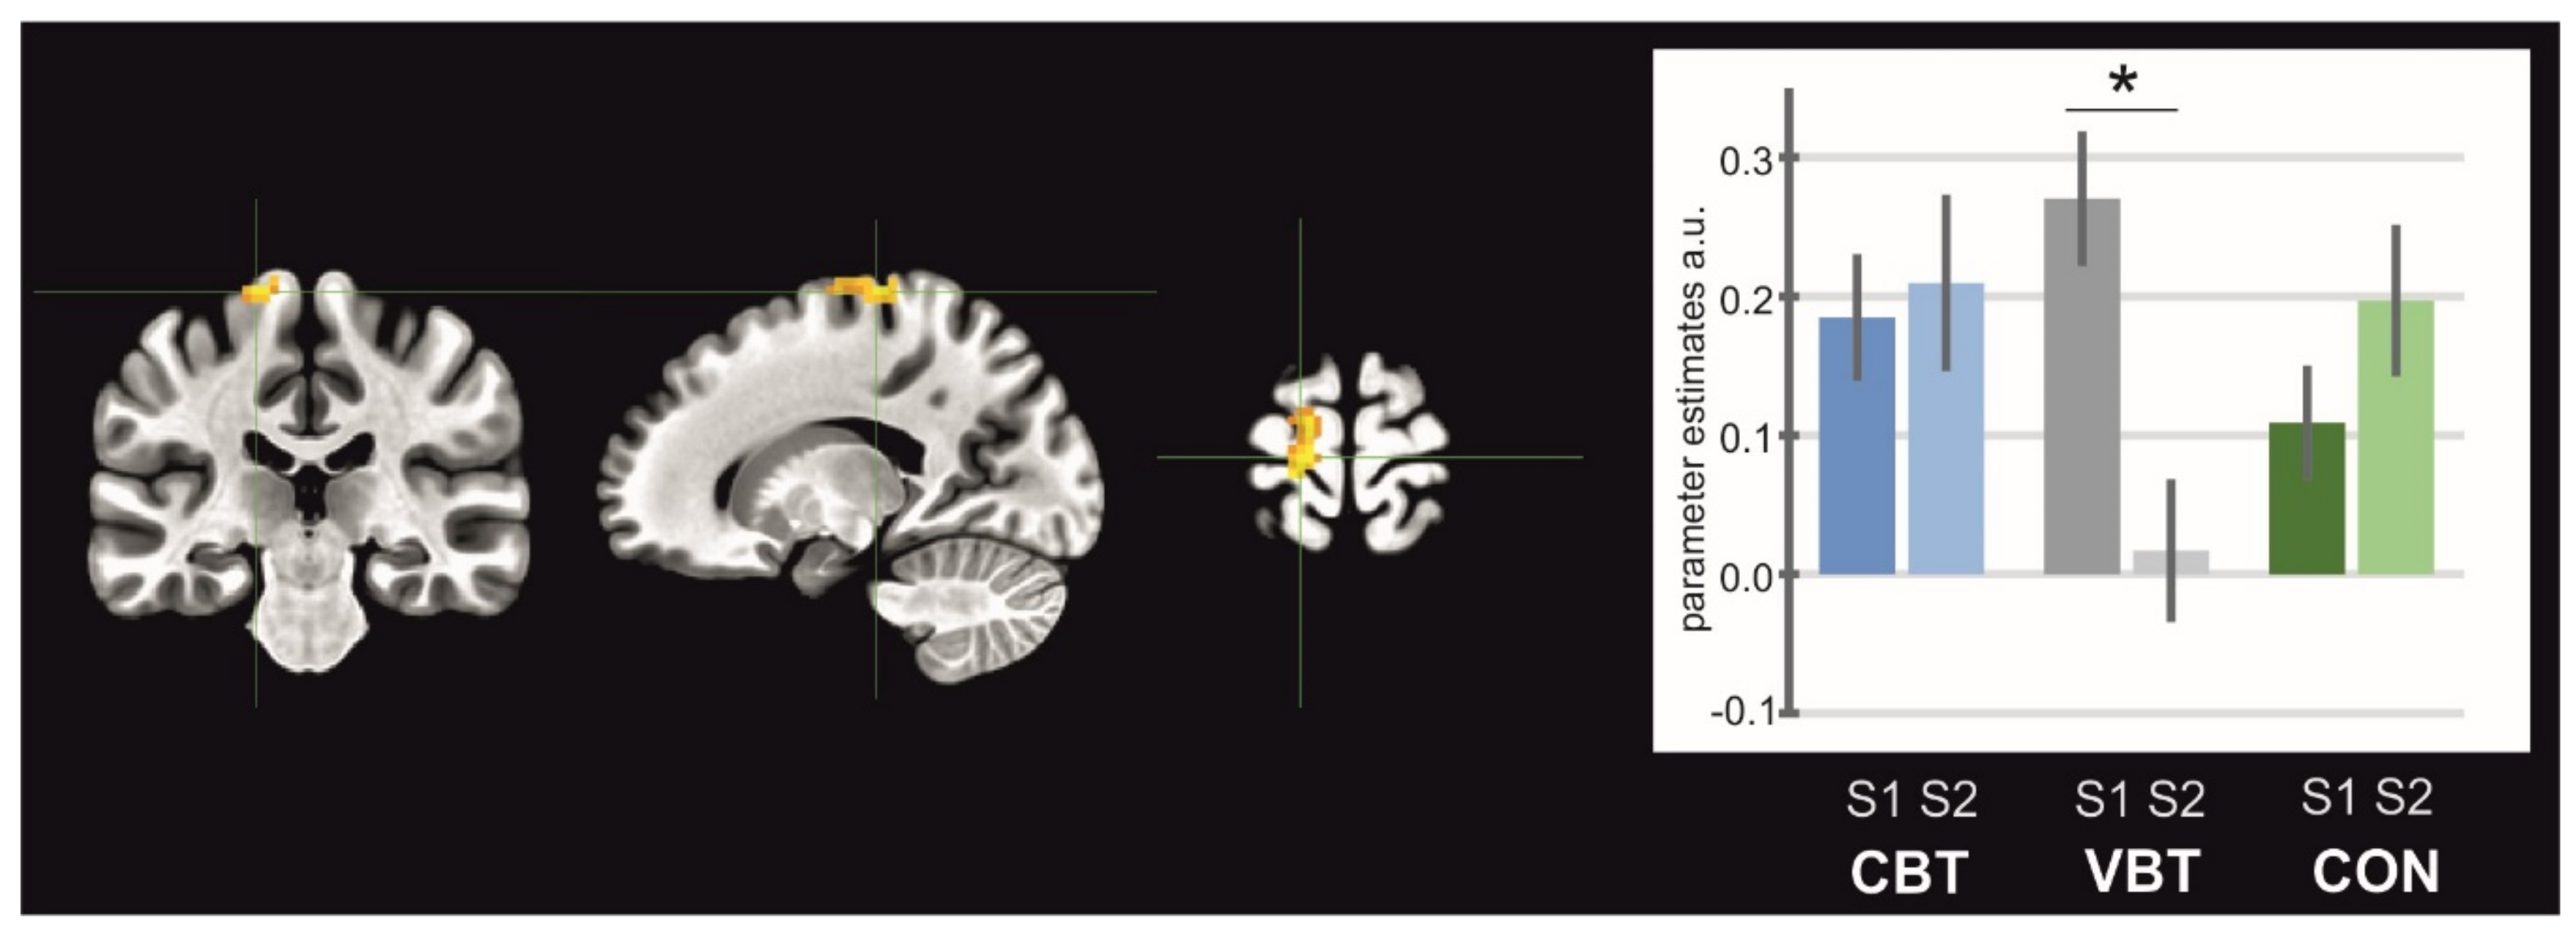

General maps of activation for MI, AO, and AOMI revealed activity in a wide set of brain areas. All significantly activated clusters are listed in Table 2, Table 3, and Table 4 for each condition, respectively. The ANOVA test revealed significant interactions of sessions and groups for SMA activity in the MI condition (Fat peak = 5.25, p < 0.05, Figure 3), where the post-hoc test indicated a significant decrease in the activity of this structure for VBT (p = 0.03). In the AO condition, there was significant interaction for the left and right supramarginal gyrus/posterior insula (left: Fat peak = 6.48, p < 0.05, Figure 4A; right: Fat peak = 6.92, p < 0.05, Figure 4B). Both clusters showed decrease in activity for the CBT group (left: p = 0.01; right: p = 0.04). In the AOMI condition, interactions of groups and sessions were found bilaterally in the middle occipital gyrus (laterally)/area V5 (left: Fat peak = 6.26, p < 0.05, Figure 5A; right: Fat peak = 8.37, p < 0.05, Figure 5B), and in the cerebellum–inferior semilunar lobule/tonsil (Fat peak = 5.47, p < 0.05, Figure 5C). Activity in the middle occipital gyrus (laterally)/area V5 significantly decreased for the CON (left: p = 0.0004; right: p = 0.02), whereas in the cerebellum—inferior semilunar lobule/tonsil activity increased for the CBT (p = 0.01).

Figure 3. Brain structure (supplementary motor area) showing interaction between groups and sessions for MI task. Note: CBT—classical balance training, VBT—virtual reality balance training, CON—control group; asterisk indicates significant differences between sessions.